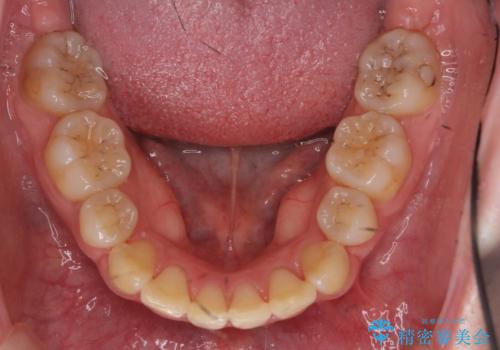

治療は長くかかりましたが、正常な形の歯をのこすことができました。

- 3年8ヶ月

20代女性 前から5番目の歯を抜歯